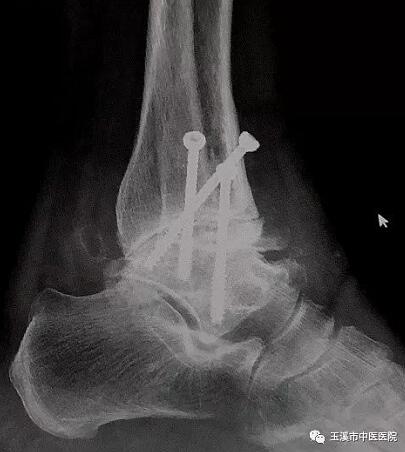

在醫(yī)務(wù)人員緊張的情況下,骨傷Ⅰ科克服種種困難,先后派出3名一線醫(yī)務(wù)人員赴千里之外的德欽縣人民醫(yī)院進(jìn)行對(duì)口援助。朱金富醫(yī)生是今年8月份去到藏區(qū)的,一到那里便積極投入工作。一位五十六歲藏族阿媽來到醫(yī)院看病時(shí),左踝關(guān)節(jié)疼痛、畸形三十余年了。 朱醫(yī)生將她收治入院,在相關(guān)檢查后,為她做了左踝關(guān)節(jié)融合術(shù)。術(shù)后藏族阿媽左踝關(guān)節(jié)功能明顯改善,生活及勞動(dòng)能力有所恢復(fù),一家人皆大歡喜。

術(shù)后X光片(左踝關(guān)節(jié)正位)